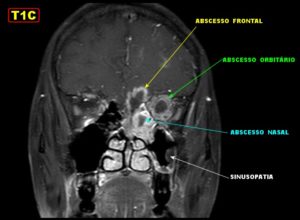

- Инфицирование полости глазницы. Это осложнение чаще всего развивается на фоне сфеноидита с вовлечением решетчатого лабиринта. Поскольку последняя анатомическая структура непосредственно контактирует с полостью глазницы, микробная флора очень легко проникает в эту полость. При этом могут формироваться ретробульбарные (расположенные за глазом) абсцессы, флегмоны. Эти скопления гноя в дальнейшем оказывают давление на глазное яблоко, приводя к его выпячиванию. При вовлечении в воспалительный процесс мягких тканей кожа вокруг глаз становится отечной, красной. Движения глазными яблоками затруднены, пациент старается держать глаз закрытым.